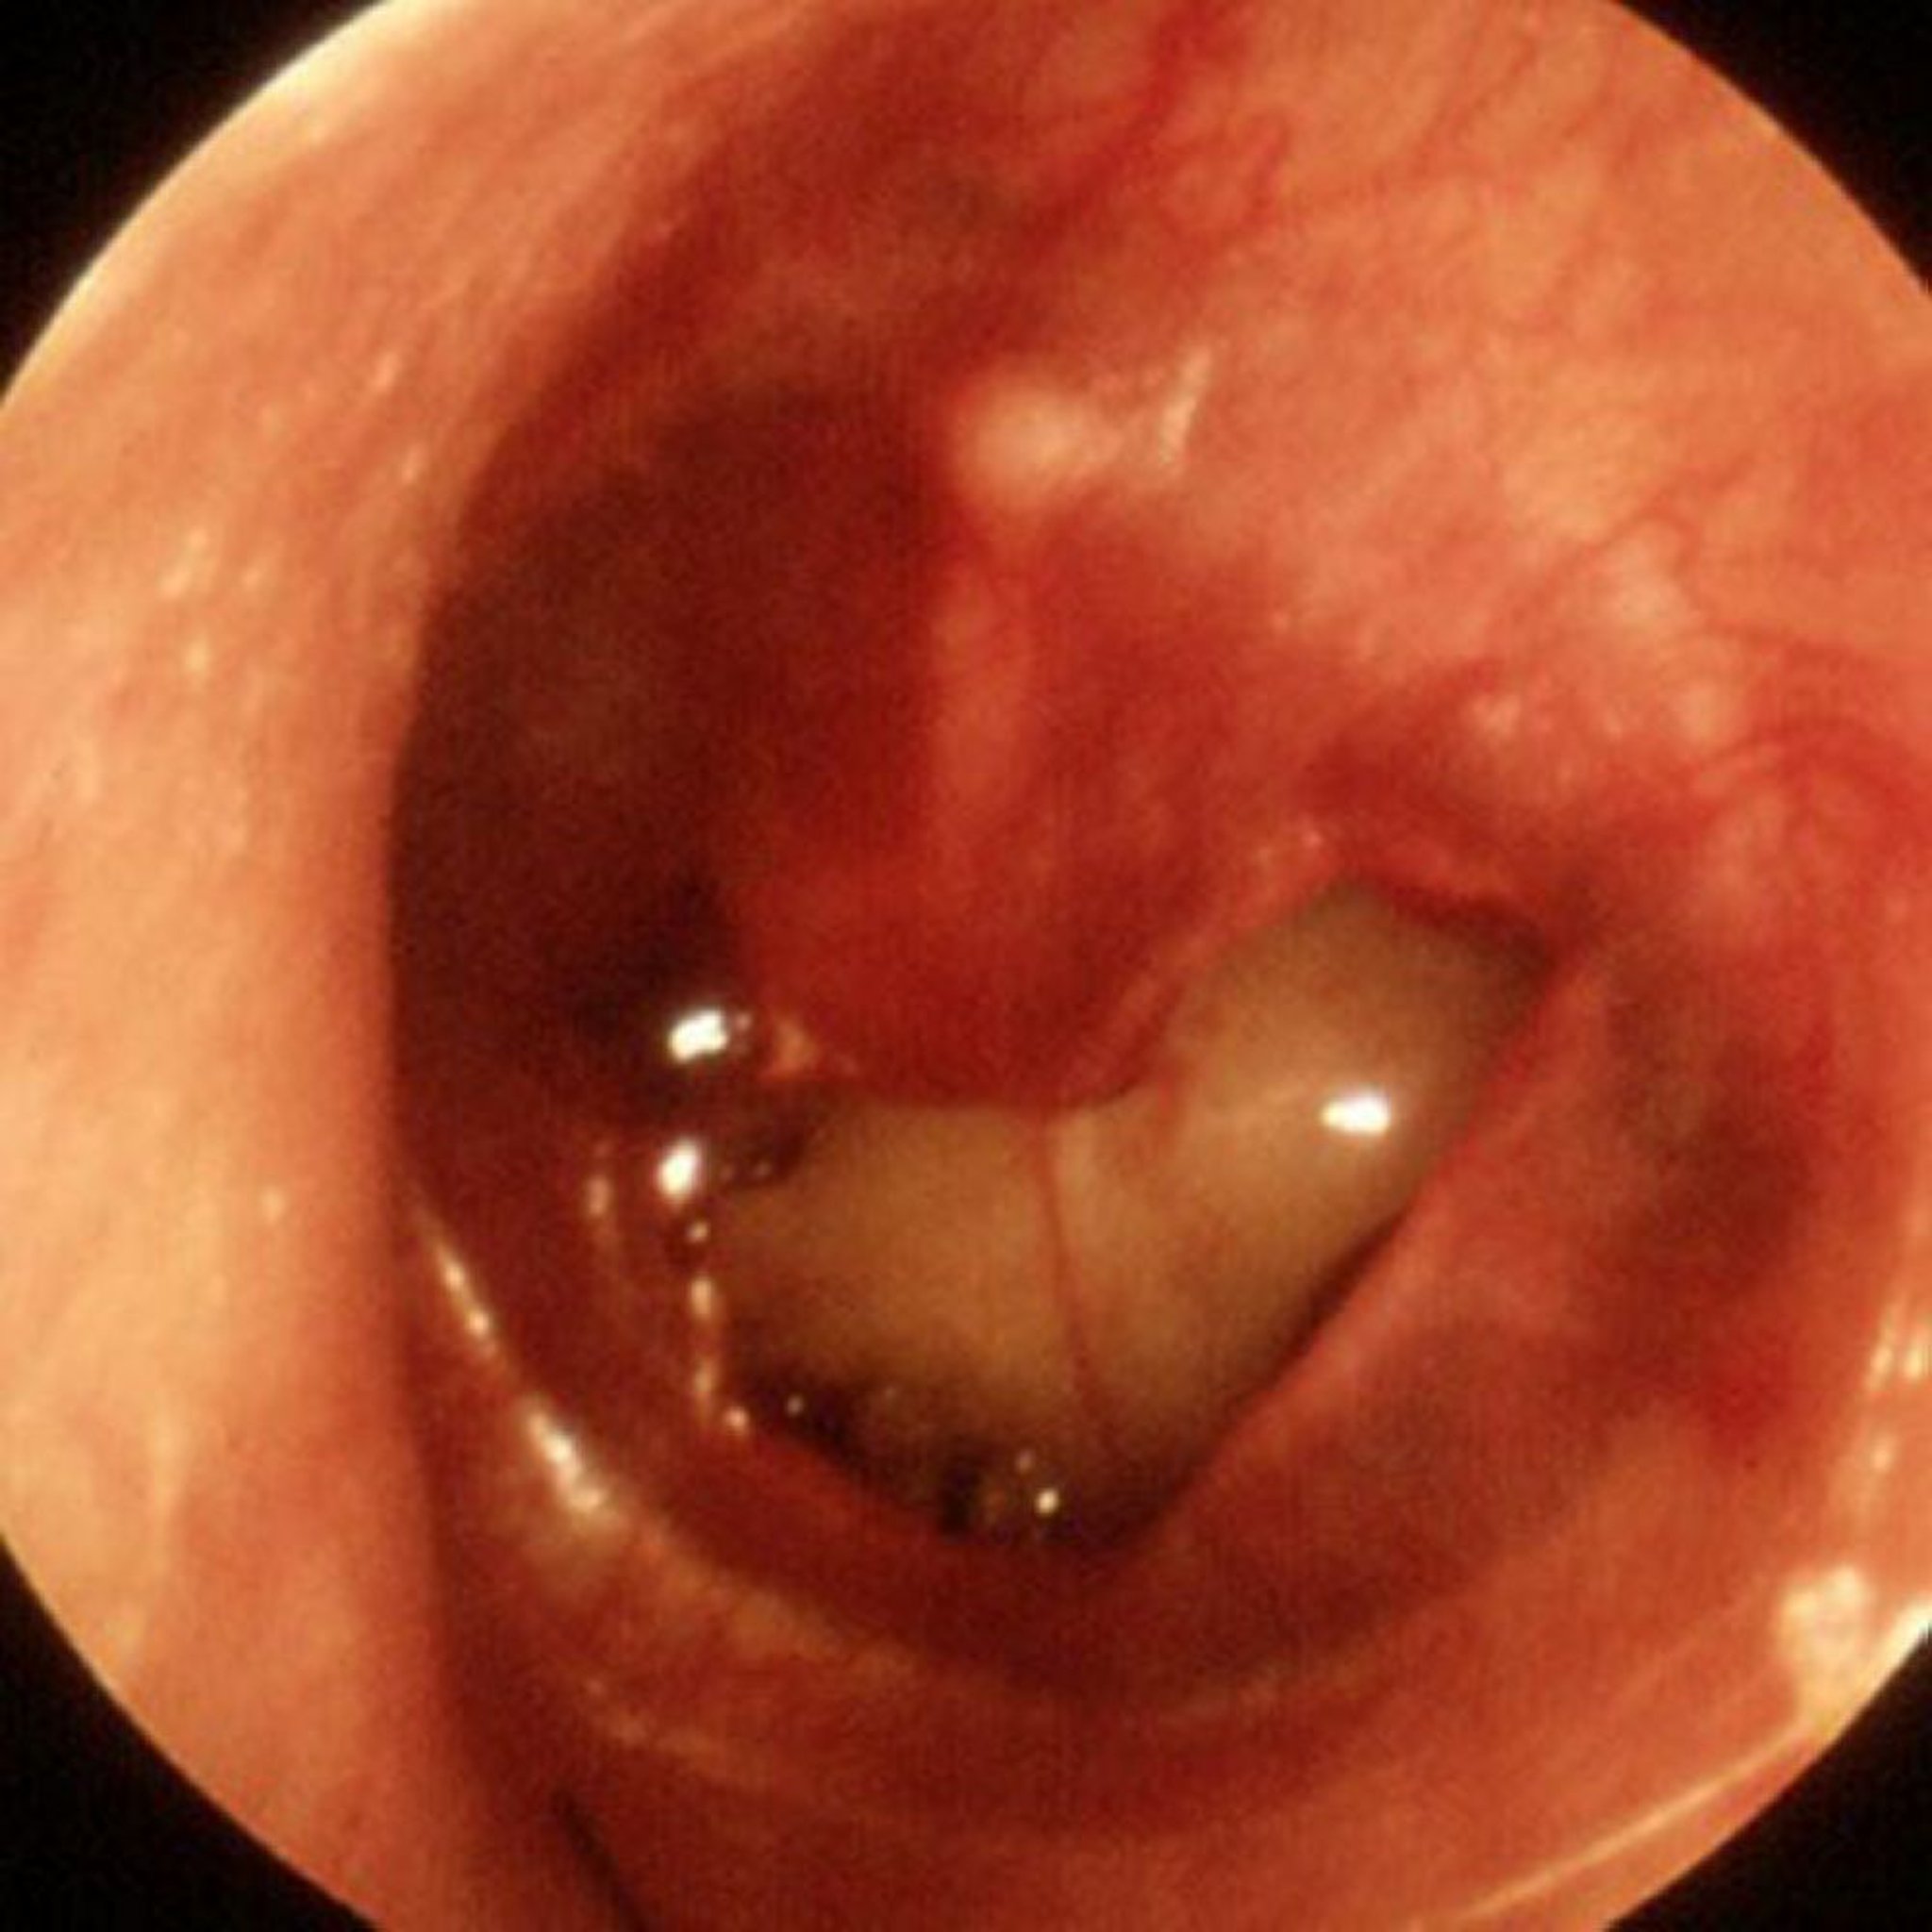

Perforazione traumatica della membrana timpanica

In questa immagine si può osservare un'ampia perforazione traumatica.

Immagine fornita da Piet van Hasselt, MD.